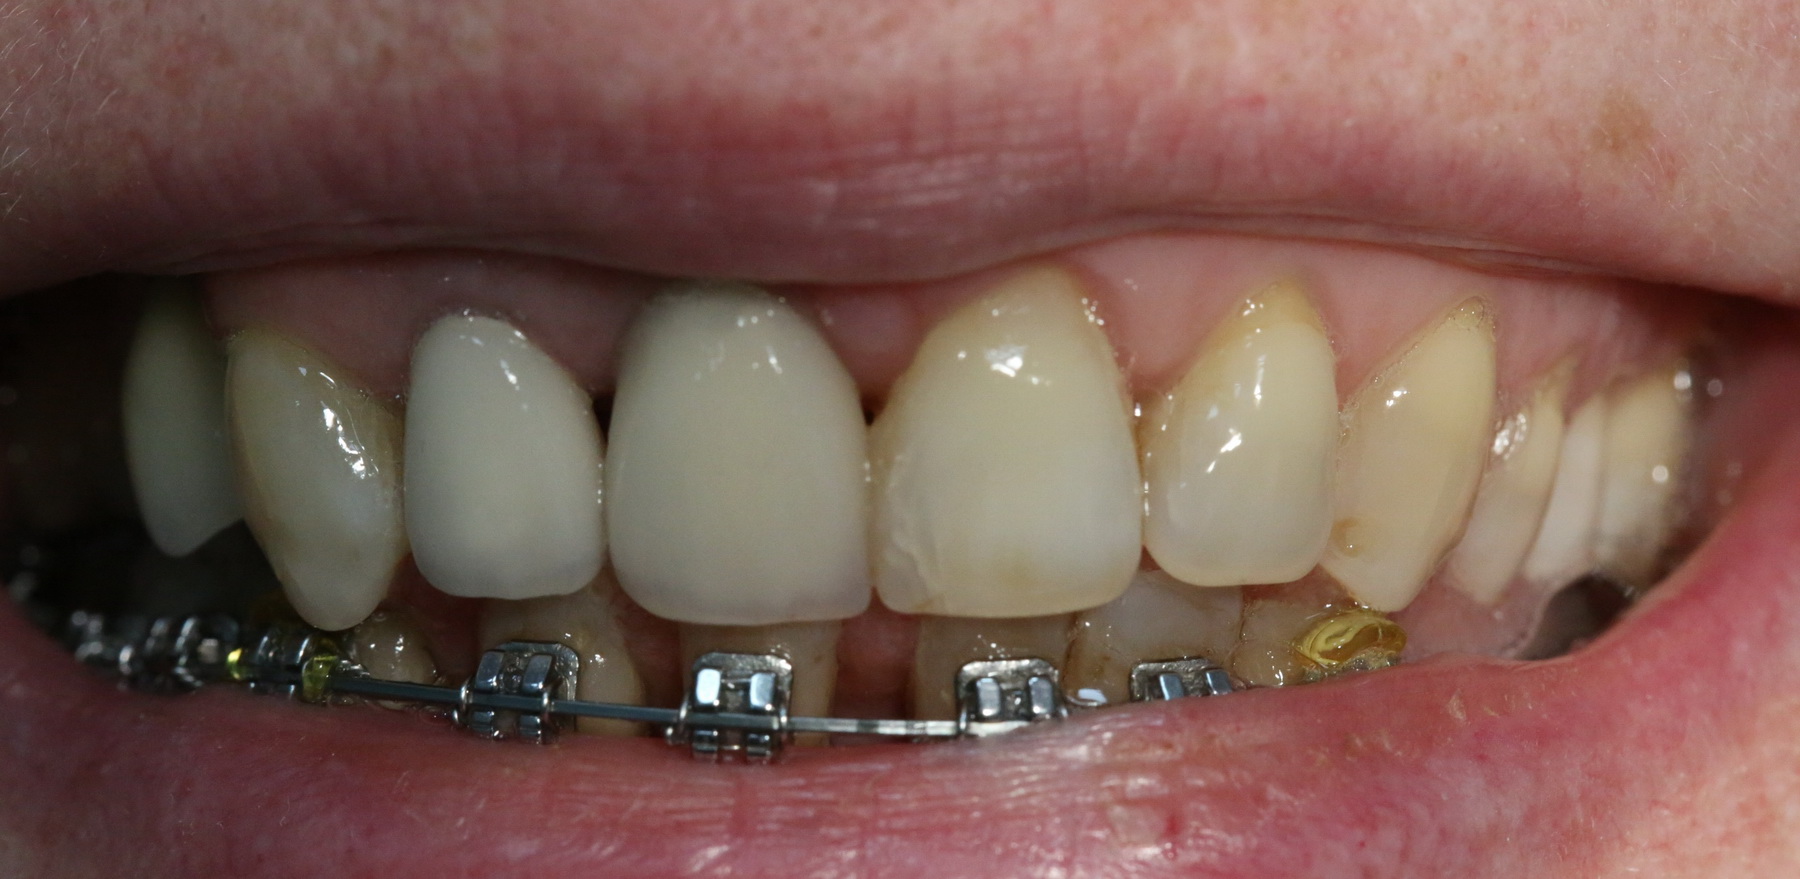

Немедленная имплантация — оптимальное решение в любой клинической ситуации